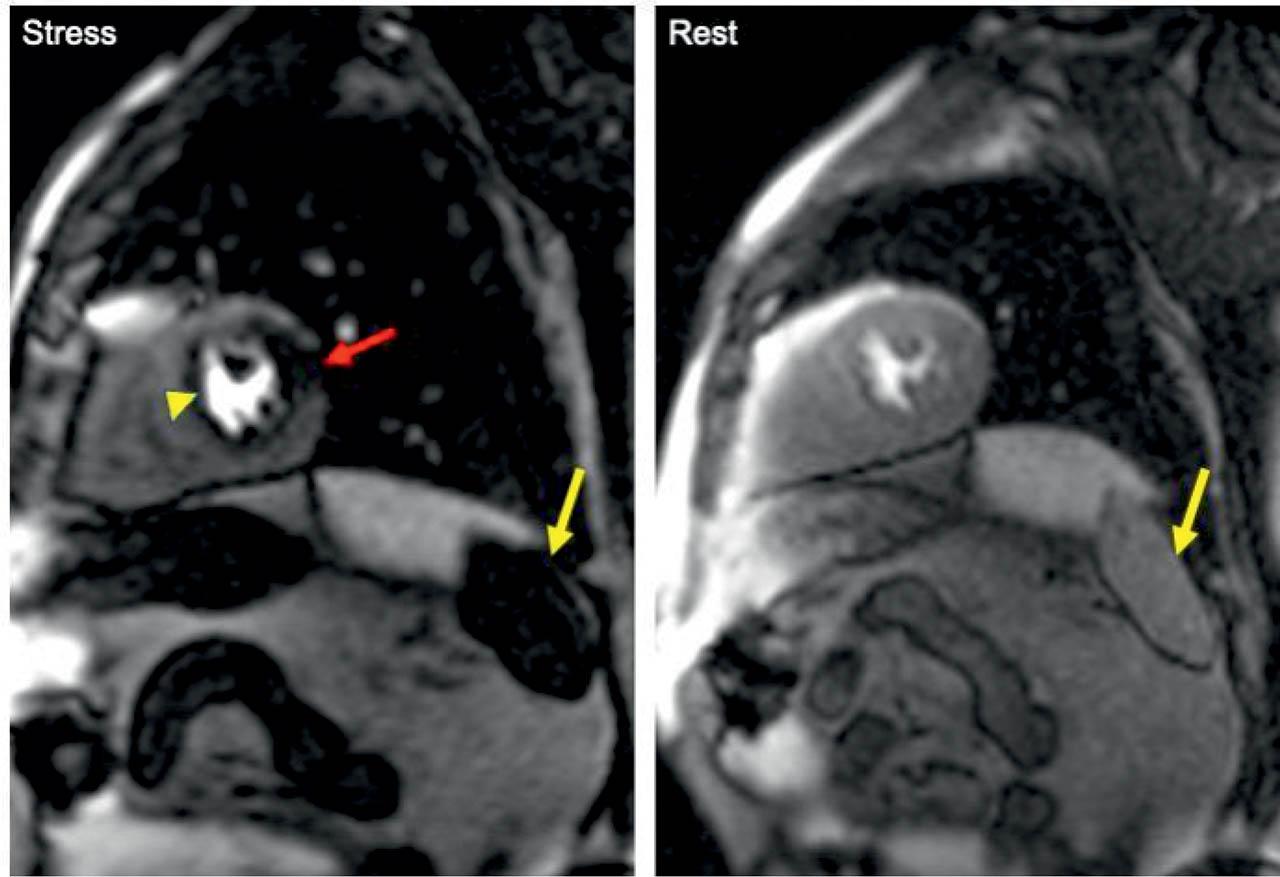

Figure 1